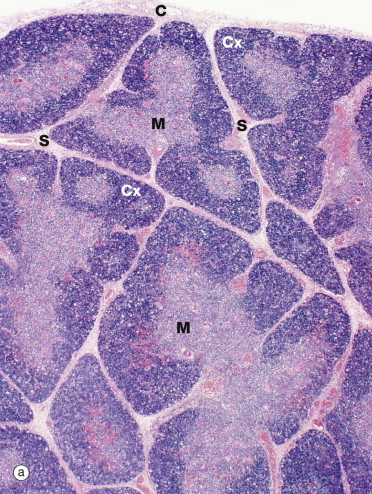

Thymus, cortex, medulla

Name the structures